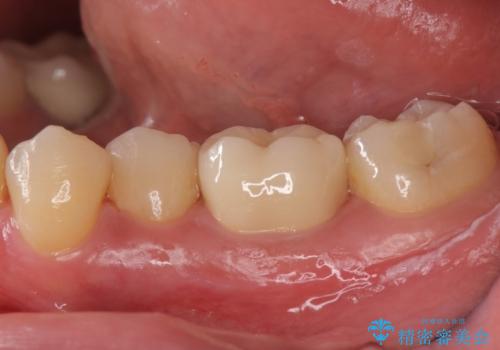

奥歯の詰め物の変色 セラミッククラウンでのやり替え